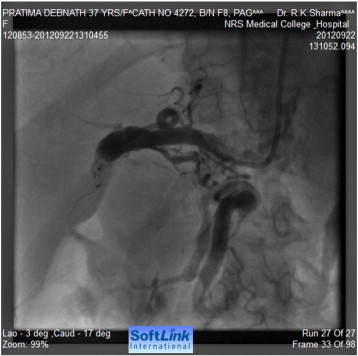

Tran-femoral catheter passage beyond the bifurcation of the abdominal aorta was not possible due to total occlusion and trans-radial aortic angiography showed a long segment of total occlusion (coarctation of abdominal aorta) just below the origin of both renal arteries, multiple dilated collaterals connecting both upper and lower aortic segments with a huge aneurysm involving gastroduodenal artery (Fig. 2, Fig. 3 ;  Fig. 4). Lower thoracic aorta was calcified and arch vessels origins and proximal aorta were normal. The blood pressure within the aneurysm was 190/110 mmHg (Fig. 5).

Aortography showing interruption of abdominal aorta below the origin of renal ...

Fig. 2.

Aortography showing interruption of abdominal aorta below the origin of renal arteries.